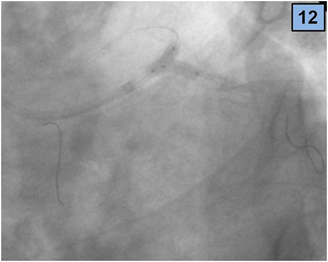

5. The procedure was successfully terminated (final TIMI 3 flow) by kissing balloon dilatation of both branches, with two non-compliant NC balloons of 3.5 x 12 mm (Figure 12). Figures 12 and 13 show the final result.

Figure 12 Final kissing balloon.